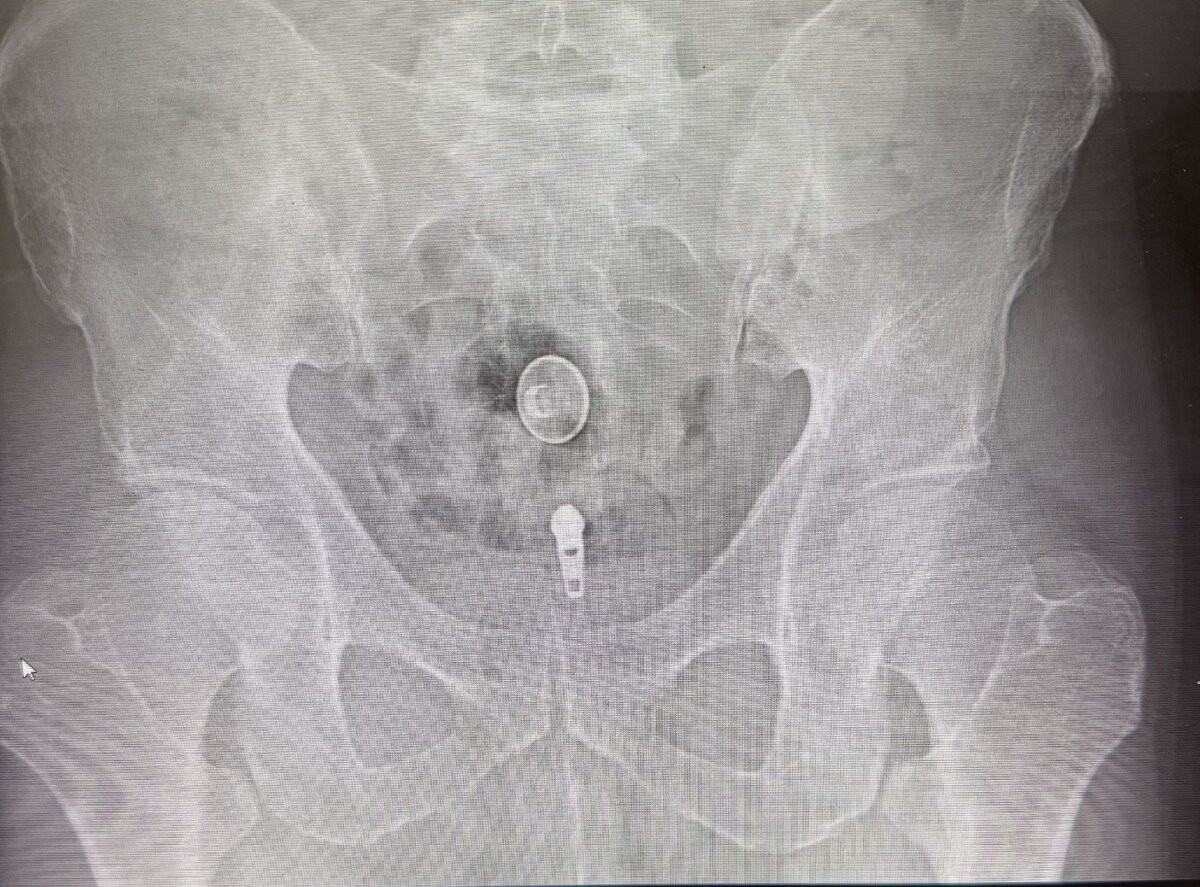

Yeah super easy. Prone AP. CLO until ischial tuberosity and lesser troch are kissing. Touch down on lateral border of ischial tuberosity, walk off to touch down on troch, pull back half the distance and you'll be in belly of muscle. If you look at axial cut of MRI you'll see what I mean.

I took the opposite approach as above as when I reviewed the anatomy on MRI sciatic and vasculature was closer to ischial tuberosity than trochanter and there was more muscle belly that overlies the lesser trochanter.

Prone, slight ipsilateral oblique to line up trajectory closer to edge of lesser tuberosity. Touch done on os, back up a few mm and inject. Slightly deep but easy injection. 100% local relief with just 1 ml of 2% lido on 2/2 patients I’ve done it on

Went great. Orthopedist was very happy with the contrast spread.

IMG_3752.jpeg